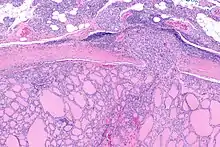

Micrograph of follicular thyroid carcinoma showing a location where the cancer grows through the fibrous capsule. H&E stain. | |

It is impossible to distinguish between follicular adenoma and carcinoma on cytological grounds. If fine needle aspiration cytology (FNAC) suggests follicular neoplasm, thyroid lobectomy should be performed to establish the histopathological diagnosis. Features sine qua non for the diagnosis of follicular carcinoma are capsular invasion and vascular invasion by tumor cells. Still, focuses of the capsular invasion should be carefully evaluated and discriminated from the capsular rupture due to FNA penetration resulting in WHAFFT (worrisome histologic alterations following FNA of thyroid).